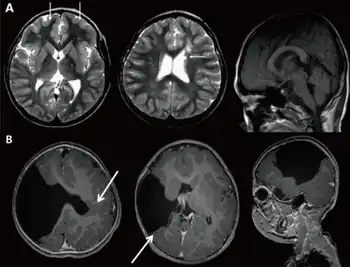

| a) Brain magnetic resonance imaging with global developmental delay (and increased serum creatine kinase) b) global developmental delay (and left hemiplegia ) | |